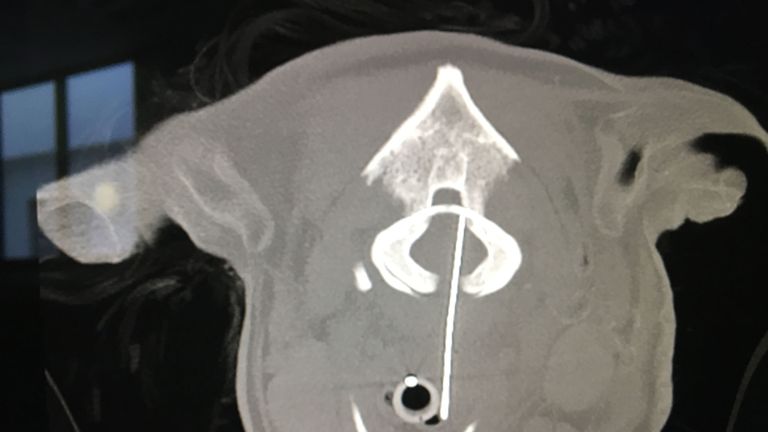

X-rays revealed Toby the Yorkshire terrier, who suffered neck pain and struggled to walk, had a sewing needle close to his brain.

A dog suspected of having a brain tumour actually had a sewing needle in his neck which had pierced his spinal cord, X-rays have shown.

The images showed he had a 7cm sewing needle with thread attached lodged in his neck, which was dangerously close to his brain.

Toby was referred to the University of Edinburgh's Hospital for Small Animals, where a CT scan was used to assess any damage to his spinal cord.